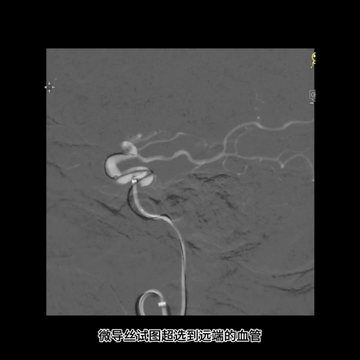

2、微导丝无法通过血栓,增强通路支撑后,单独微导管通过血栓

首先,常规微导丝操作试图通过此硬质血栓失败,后微导管抵进配合和微导丝头端重新塑形,但还是尝试失败。又调整治疗通路,上高中间管入颅增强支撑下,微导丝还是不能通过血栓,最后是谨慎操作单独用微导管通过了此硬质坚韧血栓。

M1远端栓子坚硬,微导丝难以通过;尝试微导管通过,但失败;微导丝头端重新塑形后尝试也未果。

中间管内衬.018"导丝(Command 18),并尽力推高长鞘,在增强支撑下把中间管头端推送至颈内动脉末端,以增加对微导管微导丝的支撑性。

微导丝配合下,微导管首先通过闭塞血栓位置进入M2下干,导丝跟进把微导管送至M2下干中远段,造影证实位于真腔后,送入取栓支架Trevo 4*20mm,释放支架后恢复前向血流,支架完全覆盖病变,血栓负荷较大。